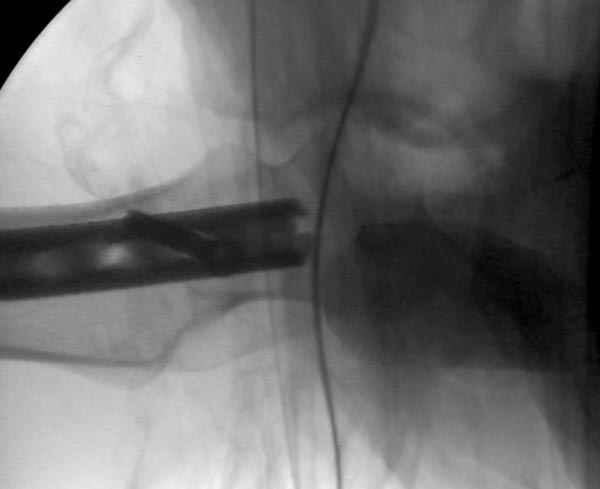

Как раз недавно у меня был примерный случай: больному 36 лет, поступил ночью, травма в результате мотоциклетной аварии, кроме чрезвертельного и спирального перелома левого бедра имеется переломы костей предплечья с этой же стороны. Скелетное вытяжение, а на следующий день больной про оперирован на ортопедическом столе с дистракцией. Чтобы не расколоть чрезвертельный перелом провели временную спицу ближе к переднему кортексу, из малого разреза костодержатель для репозиции, а фиксацию провели антиградным штифтом. Этапы операции на снимках.

Второй случай тоже репозиция из малого доступа, больному 19 лет, множественные огнестрельные повреждениия конечностей, живота и черепа, правая конечность холодная, без пульсации. Ортопедический диагноз: огнестрельный перелом правого бедра. При срочной ангиографии повреждения сосудов не подтвердилось, конечность из-за ургентности состояния больного зафиксирована временным наружным фиксатором и больной оставлен на операционном столе для срочной лапаротомии хирургической службой.

Больной долго оставался нестабильным, только на 14 день удалось заменить на антеградный интромедуллярный штифт TFN (trochanteric femoral nail) SmithNephew. После неудачной попытки закрытой репозиции, несмотря на использование "joystick", проксимальный стержень от

наружного фиксатора, (перелом начал срастаться) репозицию провели из малого доступа, затем остальные этапы операции.